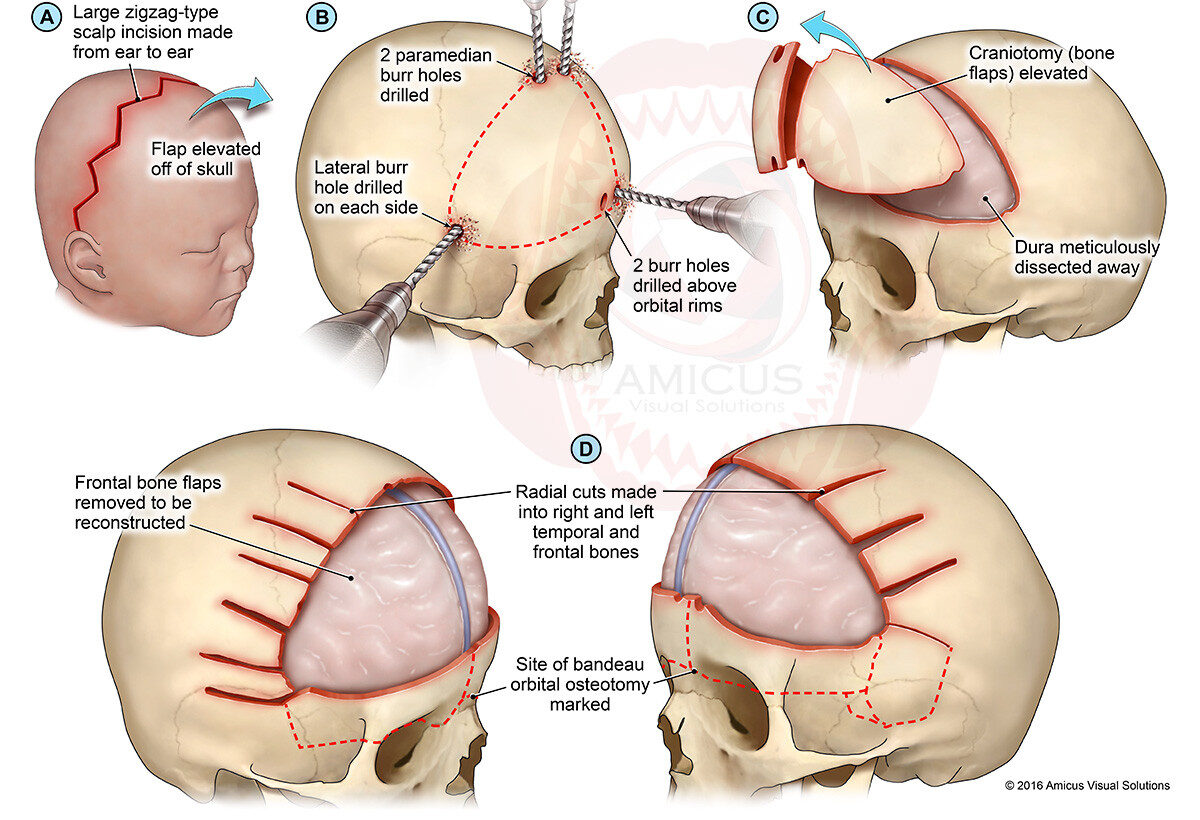

جراحة تعظّم الدروز الباكر المفتوحة للأطفال: شرح كامل للعملية، المخاطر، ونتائجها خطوة بخطوة تُعدّ جراحة تعظّم الدروز الباكر المفتوحة من أهم الحلول الطبية لعلاج انغلاق عظام الجمجمة المبكر عند الأطفال، وهي خيار شائع وفعّال